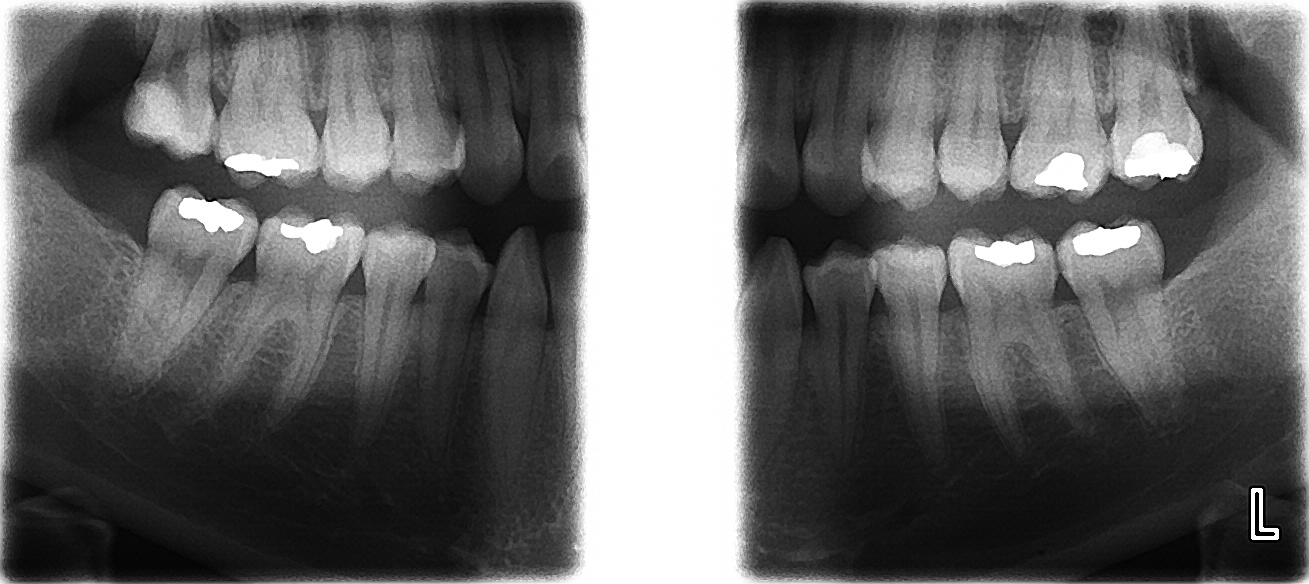

- Digitální panoramatický rentgen

- Přímo v našem stomatologickém centru zhotovujeme všem našim pacientům při vstupním vyšetření digitální panoramatický rentgen (OPG) nebo bite-wing. Běžné intraorální rentgenové snímky zhotovujeme rovněž digitálně (RVG).

- Vzhledem k poskytování komplexní stomatologické péče je naše centrum vybaveno třemi plně vybavenými ordinacemi. Zubní soupravy Planmeca, KaVo. Nadstandardní přístrojové vybavení VDW Endo IT Professional, VDW Raypex 5, VDW Reciproc, plně digitalizovaná pracoviště značky Dell. Rentgenové pracoviště, kde zhotovujeme snímky: Planmeca Pro One ( panoramatický RTG (OPG), bitewing, sinusy, čelistní klouby), Planmeca Dixi2 (intraorální snímky, bitewing)..